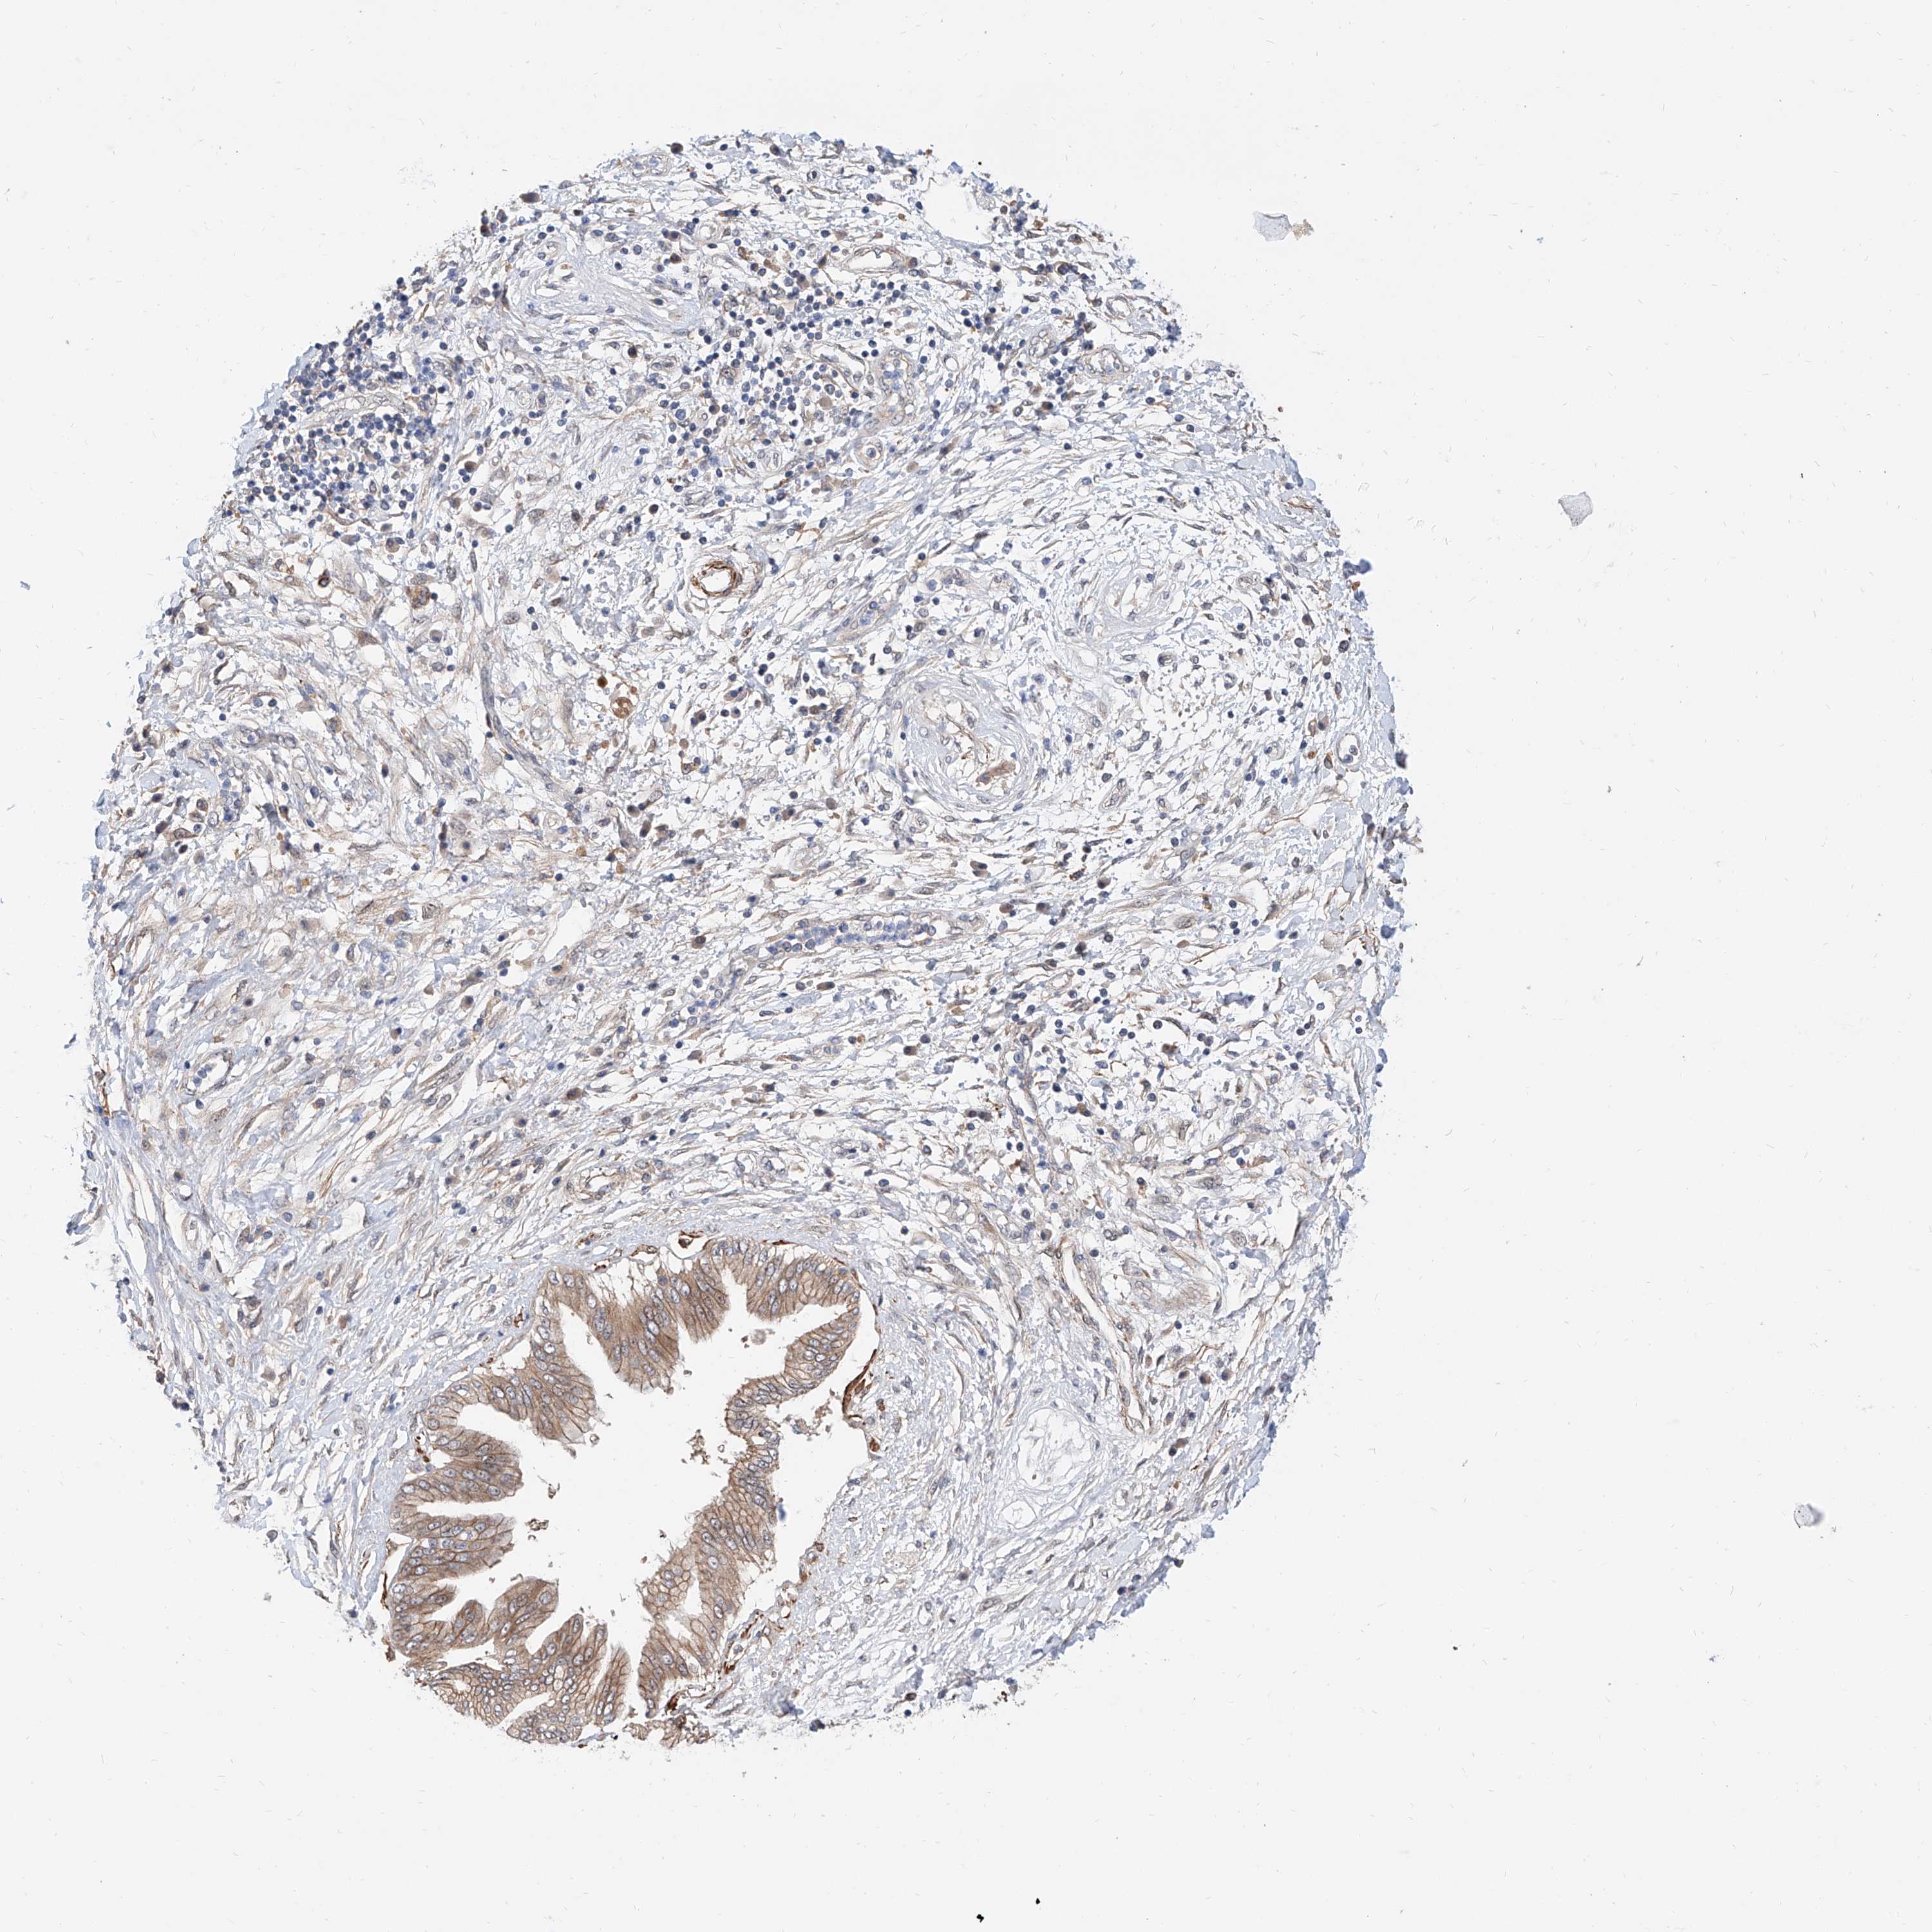

PANCREATIC CANCER - Protein expressioni

A mouse-over function shows sample information and annotation data. Click on an image to view it in a full screen mode. Samples can be filtered based on level of antibody staining by selecting one or several of the following categories: high, medium, low and not detected. The assay and annotation is described here.

Note that samples used for immunohistochemistry by the Human Protein Atlas do not correspond to samples in the TCGA dataset.

Antibody stainingi

Antibody staining in the annotated cell types in the current human tissue is reported as not detected, low, medium, or high, based on conventional immunohistochemistry profiling in selected tissues. This score is based on the combination of the staining intensity and fraction of stained cells.

Each image is clickable and will lead to virtual microscopy that enables deeper exploration of all samples and also displays staining intensity scores, fraction scores and subcellular localization as well as patient and tissue information for each sample.

Antibody HPA030625

Staining

High

Medium

Low

Not detected

Intensity

Strong

Moderate

Weak

Negative

Quantity

>75%

75%-25%

<25%

None

Location

Nuclear

Cytoplasmic/membranous

Cytoplasmic/membranous,nuclear

Adenocarcinoma, NOS